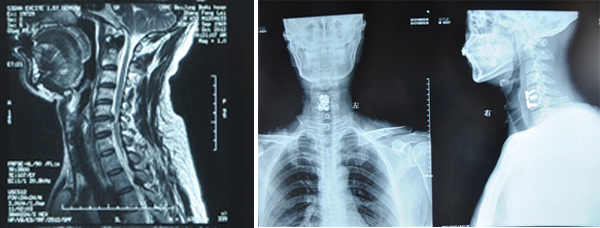

6、颈腰椎疾病手术与康复的一体化管理

遵循颈椎和腰椎疾病的手术治疗与康复的一体化管理理念,将颈椎病和腰椎疾病的手术治疗与康复有机地结合在一起,采取“术前康复——手术——术后康复”的一体化管理流程,使患者颈椎和腰椎功能康复最大化。杜良杰、李建军教授等人的研究成果主动抗阻运动疗法治疗颈椎病的临床研究获得2007年北京市丰台区科技成果三等奖。

脊髓型颈椎病术前MRI 前路减压融合内固定术后

颈椎康复器,发明人 杜良杰 专利号ZL 2005 2 0143657X

腰椎间盘突出症、腰椎滑脱、腰椎管狭窄症的手术康复一体化管理